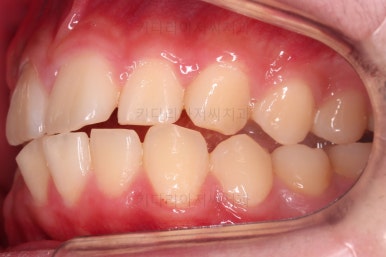

옆모습은 양호했고요.

웃을 때 드러나는 치열이 약간 삐뚤었지만 교정치료는 원하지 않으셨습니다.